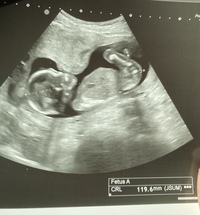

エコーで見えるダウン症の特徴とは? ダウン症の正式名称は「ダウン症候群」です。 2組1対の計46本ある染色体のうち、21番目の染色体が1本増えた染色体の突然変異によって起こり、多くのダウン症が「標準型21トリソミー」となります。 ダウン症は生まれつき見られる症候群であり、「エコー検査を通して、妊娠している間からダウン症かどうかがわかるのでは ダウン症になる確率 全体の妊娠において700人~800人の内1人がダウン症になる可能性があります。 ですが、妊婦さんの年齢が高くなるほど、ダウン症になる確率もあがっていきます。 妊婦さんの年齢が 35歳ー1/450 37歳ー1/250 40歳ー1/100 ダウン症の確定診断のための検査は、一般には妊娠後期にさしかかったころ行われることが多いようです。 妊娠後期に入る以前に、エコーなどで異常が疑われる場合でも、 妊娠後期(7ヶ月目)くらいからの検査が望ましい とか。

妊娠27週目エコー写真で見る胎児の体重や大きさ 早産になったら 妊娠中期 All About

ダウン症のエコー特徴 手足 頭 Bpd Nt Fl徹底解説 Down And Up

ダウン症胎児のエコーでわかる21の特徴 妊娠中のいつからわかる

ダウン症エコー写真 週目によるbpd Nt Flを解説 ダウン症ステーション